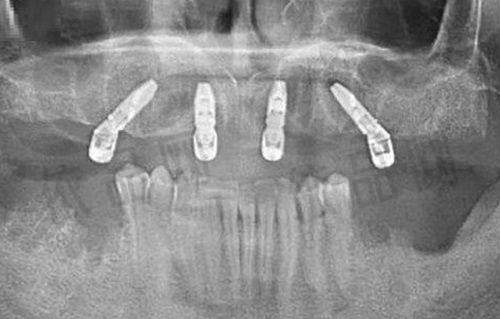

2025 年昆明种植牙医院前十强揭秘来啦,还附上各类牙齿项目价格参考,助你轻松解决牙齿问题!下面为大家详细介绍昆明种植牙医院排名前十的名单,这些医院个个实力强劲。

云南昆明固齿口腔门诊部在种植牙领域有着较高的水准,不管是当地居民还是外地患者,想要进行种植牙都会来这里询问,能享受到医生的优质服务。

昆明美奥口腔医院在种植牙方面技艺高超,医师技术娴熟,能有效减少顾客的痛苦,还能轻松完成高难度的种植任务,深受大家青睐。如果您有牙齿方面的困扰,不妨来这家机构检查,相信能满足您的需求。

云南昆明柏德口腔门诊部实力雄厚,能做到当天种植牙齿,当天即可使用,因此受到众多患者的青睐与认可。

昆明尚爱韩美口腔是一家与国内外接轨的牙齿诊疗机构,顾客可以在这里接受国外种植师的诊疗服务。这些种植师经验多,大多拥有 20 多年的从业经验,技术值得信赖。